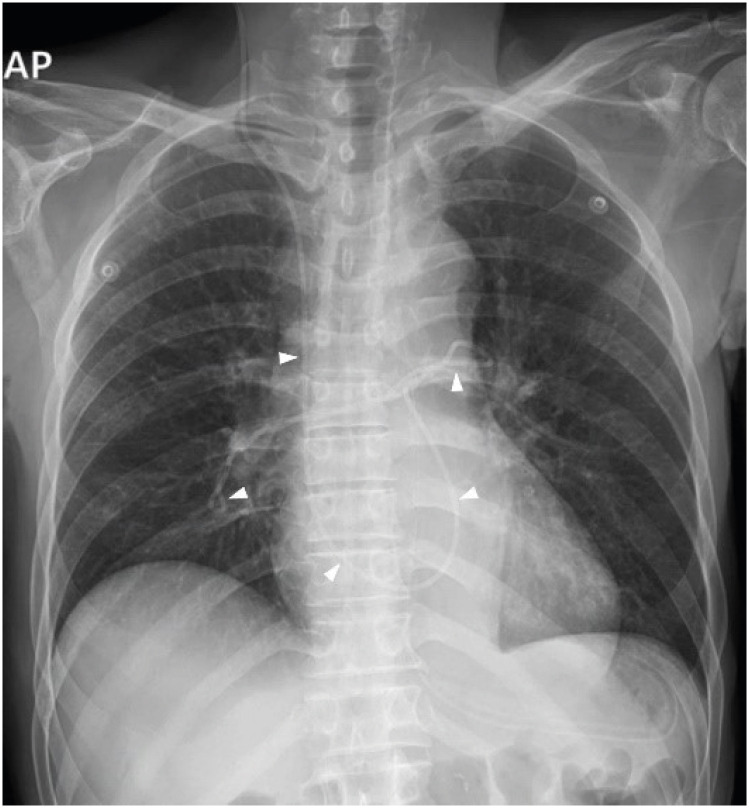

The treatment of hydrocephalus with a ventriculoperitoneal (VP) shunt can lead to complications such as shunt migration. A 67-year-old male, who had previously undergone VP shunt surgery for normal-pressure hydrocephalus, presented approximately five years later with symptoms of general weakness and abdominal pain. Imaging revealed shunt malpositioning, with the catheter passing through an abnormal route to the heart. The catheter was successfully removed under fluoroscopic guidance while monitoring patient's electrocardiogram to prevent potential secondary complications. Although rare, cardiac migration of VP shunts can lead to life-threatening secondary complications. Our case highlights the possibility of delayed upward migration of the shunt catheter in patients with VP shunts, emphasizing the need for various strategies to address and manage this issue.

Abstract Image